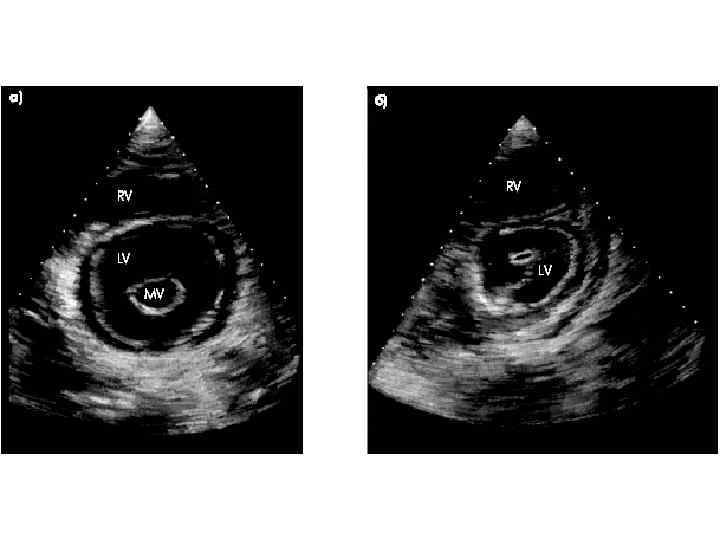

Митральный стеноз (стеноз левого атриовентрикулярного отверстия) Митральный стеноз – порок сердца, при котором суженное митральное отверстие служит препятствием для изгнания крови из левого предсердия в левый желудочек.

Механизмы компенсации 1. Повышается давление в полости левого предсердия (от 5 мм рт. ст. в норме до 20– 25 мм рт. ст. ); увеличивается разность (градиент ) давления левого предсердия — левого желудочка, что облегчает прохождение крови через суженное атриовентрикулярное отверстие. 2. Удлиняетс я систола левого предсердия; кровь в левый желудочек поступает в течение более длительного времени. 3. Гипертрофия мышцы левого предсердия — является следствием длительной перегрузки предсердия давлением. 4. Прогрессирующее уменьшение площади левого атриовентрикулярного отверстия вызывает дальнейший рост давления в левом предсердии, что приводит к ретроградному повышению давления в легочных венах и капиллярах. Повышается давление в легочной артерии, развивается пассивная, ретроградная, венозная, посткапиллярная легочная гипертензия. Давление в легочной артерии 30– 60 мм рт. ст. (в норме до 25 мм рт. ст. ). Развивается гипертензия правого желудочка. 5. Дальнейший рост давления в левом предсердии и легочных венах вследствие раздражения барорецепторов вызывает рефлекторное сужение артериол (рефлекс Китаева). Это ведет к значительному повышению давления в легочной артерии (60– 200 мм рт. ст. ), развивается активная, артериальная, прекапиллярная гипертензия. Рефлекс Китаева выполняет защитную роль, предохраняя легочные капилляры от чрезмерного повышения давления и выпотевания жидкой части крови в полости альвеол.